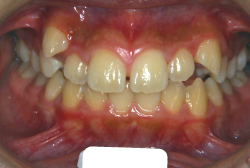

「歯並びの凸凹を直したい」という主訴で来院したケースです。診断の結果、たしかに「叢生」という隙間が足りないと言うことが原因の凸凹症例でした。

しかし、それ以上に問題なのは「前歯の噛み合い方が深すぎる」という症状で、初診の歯の正面写真を見ると下の前歯が全く見えません。こういう症状を矯正学では「過蓋咬合(かがいこうごう)」と言います。過蓋咬合を放置すると、将来的に顎関節に悪影響を与えるとされており、顎関節症の原因因子の一つです。また下の前歯の先端が、上の前歯の裏側の歯茎と強く接触するため、歯周病の原因にもなります。

検査の結果、凸凹が軽症なため非抜歯で矯正すること可能と判断、マルチブラケット装置にて治療しました。治療後は歯並びが綺麗になっただけでなく、噛み合わせ的にも正しい状態が確立しています。